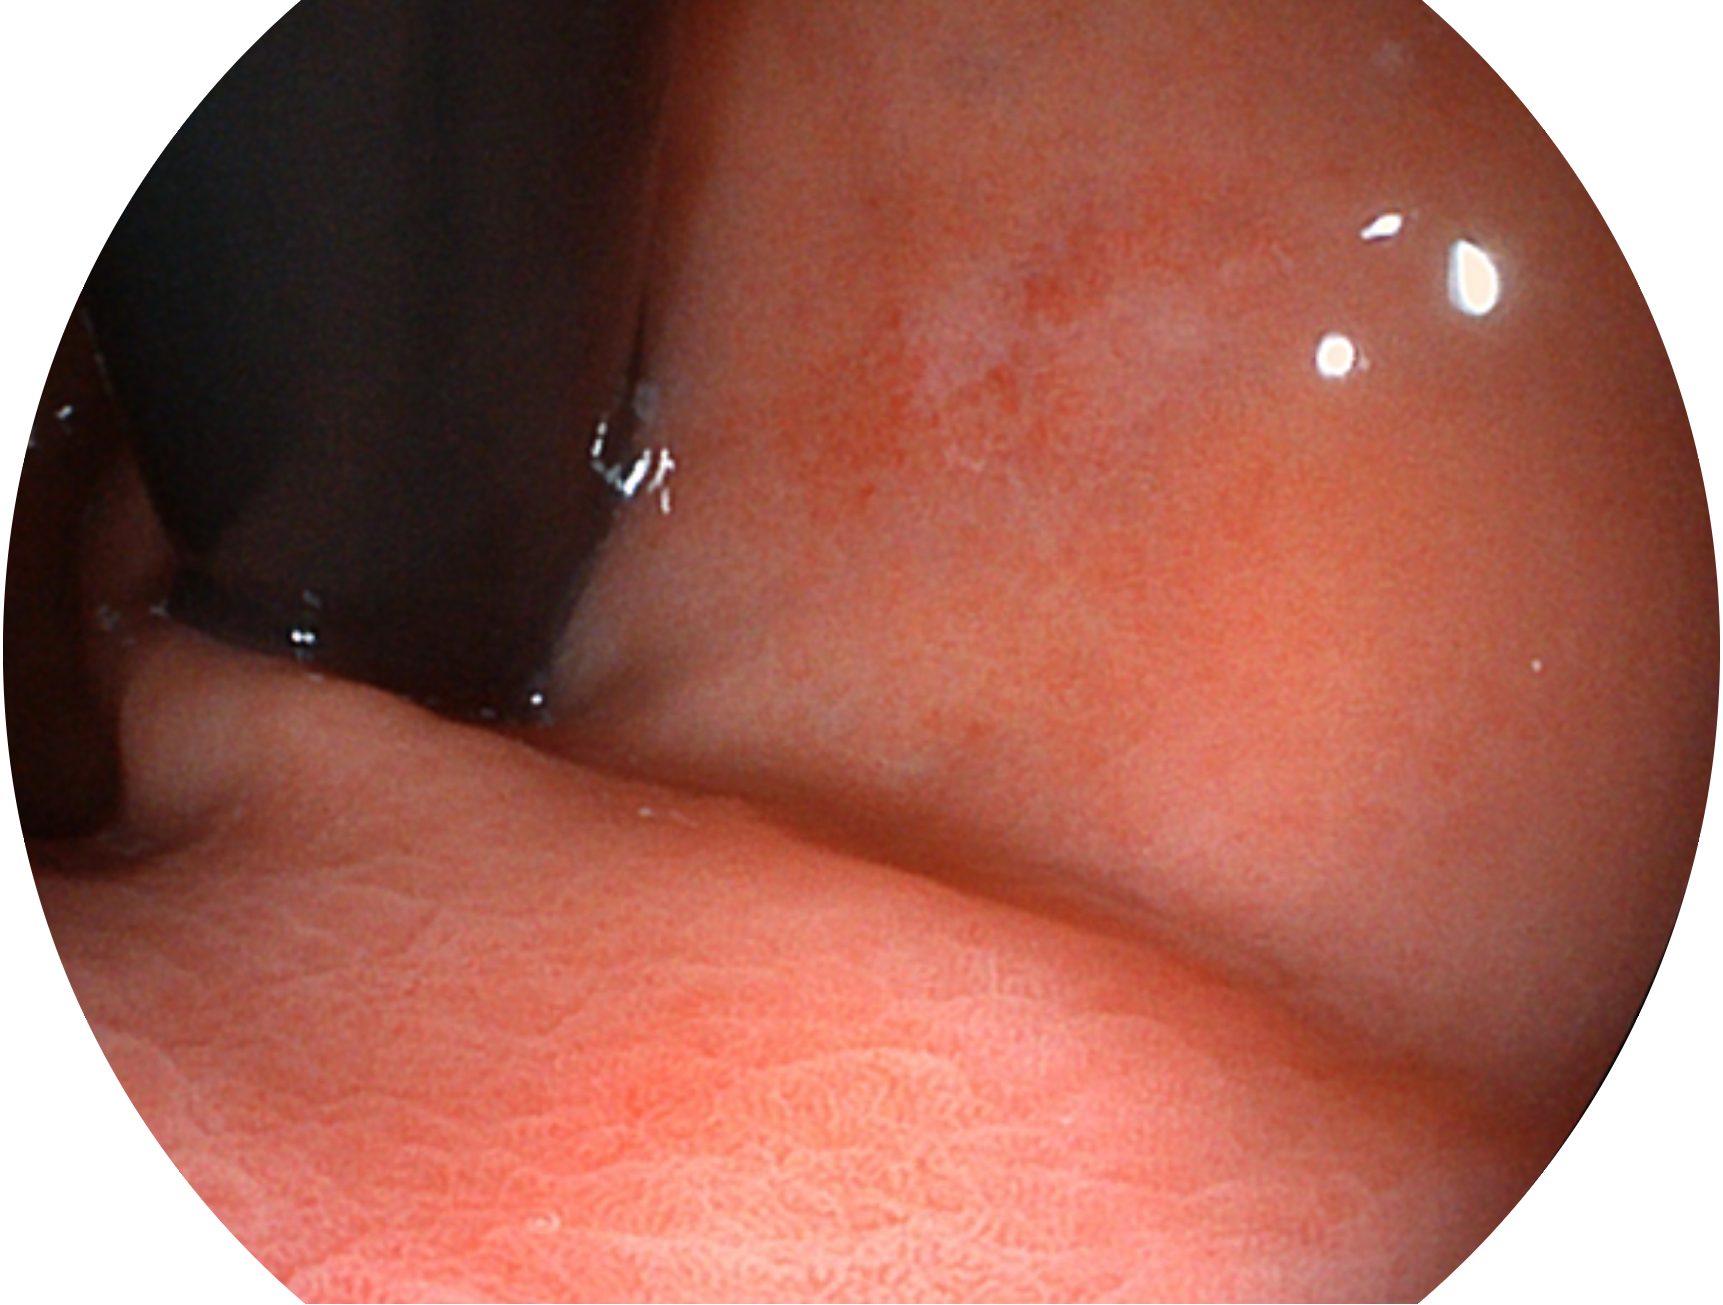

银河优越会新开发的内镜染色技术,主要是基于多波长LED 光源的开发,VLS-55Q 四波长LED 光源是由四个不同颜色的LED光按照相应照明模式所规定的特定发光比例进行合束后形成,合束后形成的照明光的光谱由红光、绿光、蓝光及蓝紫光这四个不同的波段范围构成。具有更高光谱自由度,通过光谱比例的控制,实现了聚谱成像技术,英文全称为“Spectral Focused Imaging, SFI”,缩写为“SFI”和光电复合染色成像技术,英文全称为“Versatile Intelligent Staining Technology, VIST”,缩写为“VIST”。